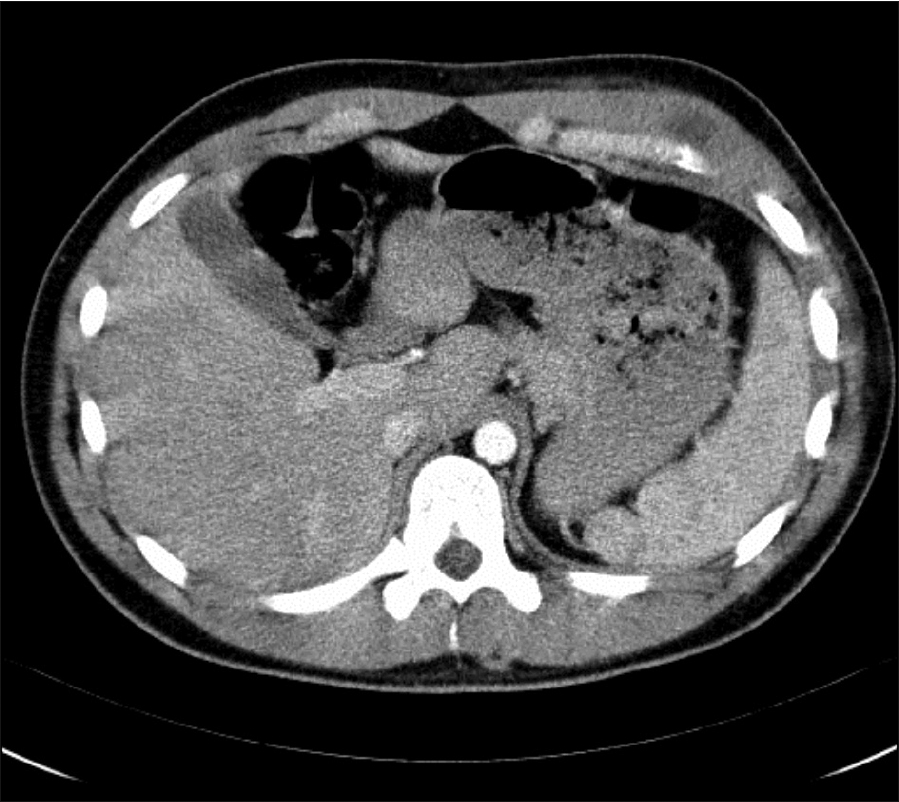

Figure 2: CT thorax – low attenuating lesion in overlying anterior ribs/costochondral areas 5 to 7 with associated intercostal muscle thickening

Figure 2: CT thorax – low attenuating lesion in overlying anterior ribs/costochondral areas 5 to 7 with associated intercostal muscle thickening(click to enlarge)

A CT evaluation showed a low attenuating lesion overlying the anterior fifth-seventh ribs associated with intercostal muscle thickening (Figure 2), which may represent resolving haematoma or abscess formation.